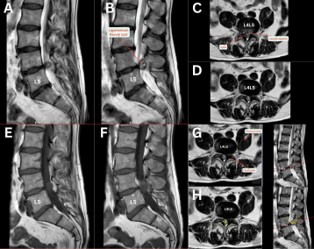

MRI of a 67-year-old patient presenting with disabling right sided L5 radicular pain without motor deficit.

Figure 1: MRI.

Sagittal (Figure 1A,1B,1E,1F) and axial (Figure 1C,1D,1G,1H) MRI revealed an extradural cystic lesion with a broad base insertion adjacent to the ligamentum flavum at L4/L5, appearing well-demarcated, hyperintense on T2-weighted and hypointense on T1-weighted sequences. The lesion significantly compresses the right L5 root and narrows the spinal canal.

Surgical excision and histology confirmed a fibro-collagenous ligamentum flavum cyst without synovial lining.